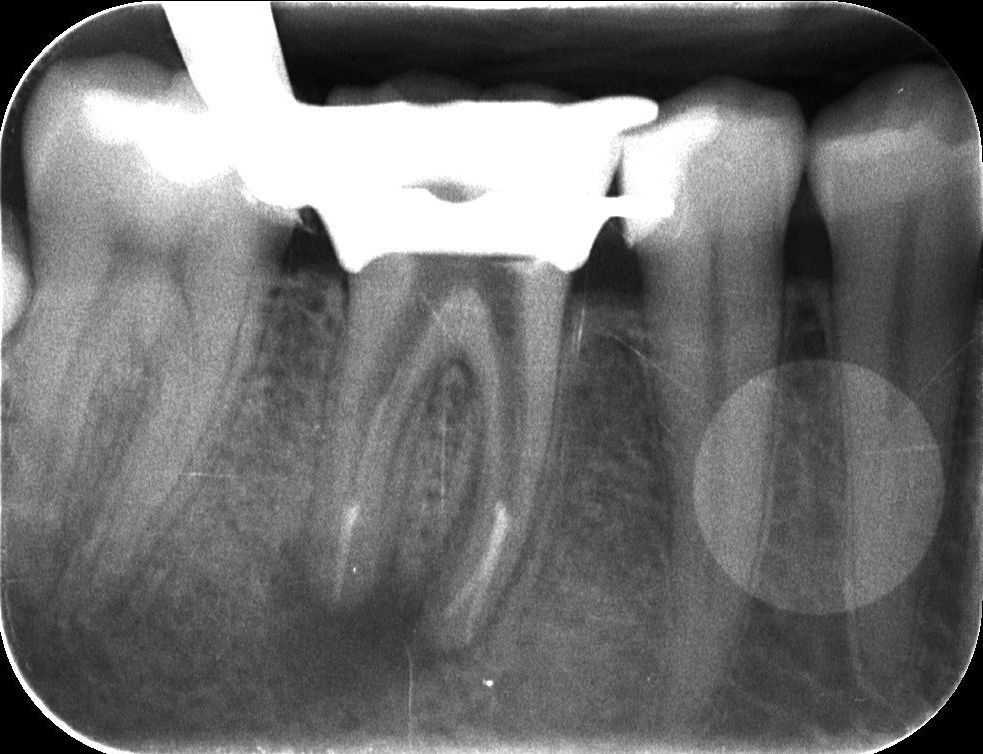

2. röntgenfelvétel

A régi gyökértömés eltávolítása, illetve a csatornák teljes feltárása után a későbbi gyökértömő „pálcikákkal” készült röntgenfelvétel. Ezen ellenőrizzük a gyökértömés készítése előtt, hogy valóban jól dolgoztunk-e, és hogy sikerült-e minden csatornának eljutni a végéig.